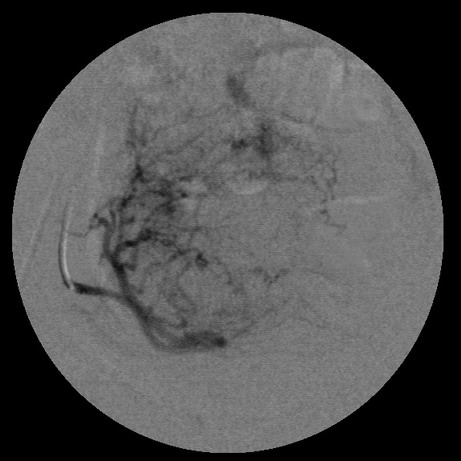

女,35岁,子宫多发肌瘤

子宫动脉增粗,分支数量增多,迂曲,染色明显并排空延迟

以后会有代偿血管生成的